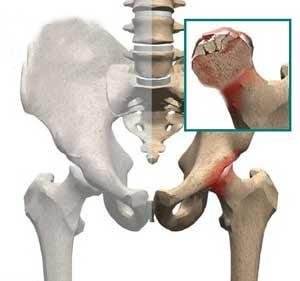

儿童骨头坏死是什么

儿童股骨头坏死,又称股骨头骨骺软骨炎、股骨头无菌性坏死或扁平髋。是儿童常见的原因不明的软骨病,多发于2~12岁儿童,以退行性变或坏死开始,继后出现再生或重新钙化,最终出现股骨头的坏死。一开始表现为膝关节-髋关节痛,步行不便或跛行,患髋不能屈伸、内收。因为有的很隐匿,孩子只是有点疼,跛行两天,有像是没事了,只有磁共振才能发现股骨头的缺血水肿,本病早期诊断早期治疗十分重要,但又有几个家长愿意让孩子因为髋关节有点疼痛就去做磁共振呢?

1,对于儿童期出现的股骨头坏死主要与发育有关,特别是有髋关节半脱位或者是先天性的髋关节脱位,会导致股骨头部位出现异常的摩擦挤压,从而破坏股骨头的软骨面和周围的血液,就会导致股骨头坏死。

2,还有就是见于外伤,特别是*力暴**导致了股骨头股骨颈部位的骨折,髋关节脱位复位后,如果说治疗不当,也有说法是因为关节囊内出血,压力增大引起,后期也容易引起股骨头部位的血液破坏,从而引起了股骨头坏死的情况。

3,还有就是见于先天性髋关节发育不良的患者,也会导致有股骨头坏死情况的发生。